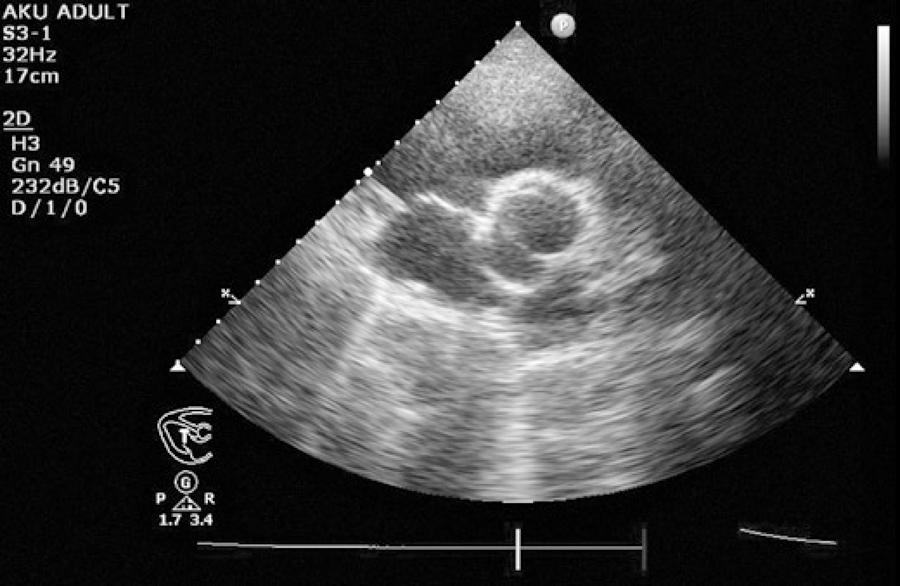

A 27-year-old female was admitted to our clinic with a complaint of decreased vision since childhood. Uncorrected visual acuity was 1/10 for both eyes. The best-corrected visual acuity was 2/10 in the right eye with -10.00/-5.00 × 165° diopter correction and 3/10 in the left eye with -7.00/-4.00 × 10° diopter correction. Ocular movements were normal. Intraocular pressure in both eyes as measured by Goldmann applanation tonometry was 14 mmHg. Anterior segment examination revealed a normal iris and no coloboma. After dilatation of the pupils, bilateral lens coloboma located in the inferior temporal regions was detected (Figure 1). Other ocular examinations, including fundus examination, fluorescein angiography, and optical coherence tomographic imaging revealed normal findings (Figure 2). Visual field testing using the 24-2 full-threshold strategy of the Humphrey Field Analyzer did not detect any defect. Medical and family histories were unremarkable. Because of the risk of an associated systemic disease, the patient was examined thoroughly by specialists in the departments of neurology, cardiology, internal medicine, and genetics. Neurology and internal medicine work-up did not reveal any abnormalities. Chromosomal analysis was normal, showing the 46 XX karyotype. In the cardiology work-up, echocardiography revealed a bicuspid aortic valve accompanied by an abnormal aorta (Figure 3). Coronary angiography or computerized tomographic angiography for imaging of other possible cardiac anomalies was not performed.